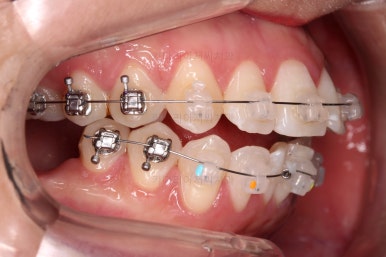

장치를 부착해서 가지런하게 하고요.

이번 부산사랑니교정 환자분이 선택하신 장치는 데이몬 클리어라고 하는 자가결찰 세라믹 장치인데요.

현존하는 세라믹 장치 중에 가장 심미적인 장치입니다.

철사를 잡아주는 뚜껑은 금속으로 되어있는 클리피씨나 엠파워 클리어에 비해 뚜껑까지도 세라믹으로 되어있기 때문이죠.

대신 금속 성분이 많은 장치보다는 부피가 확실히 커지게 되는데요.

돌출입의 경우 초반에는 입이 더 나와보일 수 있고요.

입이 더 나오는 정도는 사람마다 매우 차이가 큽니다.

참고만 해주세요.

윗니도 발치를 했고요.

발치공간을 서서히 줄여 나갑니다.

입매 변화도 신중하게 체크합니다.

윗니는 어느 정도 틈이 많이 줄었는데요. 아랫니는 기약이 없죠.

이때가 교정을 시작한지 8개월이 지난 시점인데요.